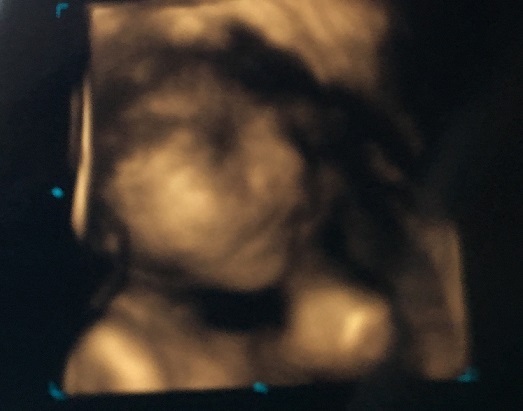

29週3日(29w3d・女の子)|ヨシリス さん(35歳)

エコー写真撮影時のエピソード:

29週の写真です。あまり健診時には顔を見せてくれなかった中で、唯顔らしい顔を見せてくれた1枚。

左手を目に当てて眠たいよ〜といってるように見えます。娘と分かってからようやく見れたお顔だったので、可愛いか美人かどっちかを主人と話した懐かしい思い出です!